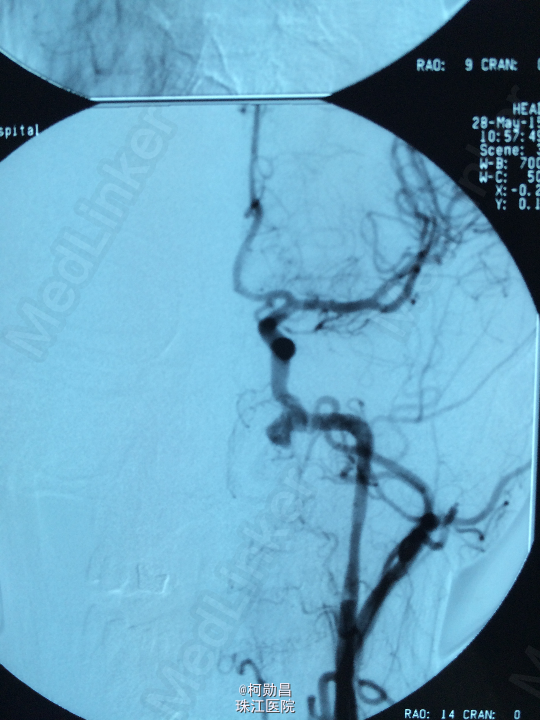

诊断:颈内动脉假性动脉瘤破裂 处理:急诊行DSA检查,提示颈内动脉海绵窦段动脉瘤形成并破裂向鼻腔引流,予血管内栓塞治疗,将动脉瘤腔堵塞,患者出血停止。